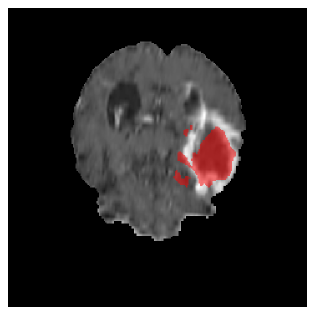

Appendix A Qualitative results

Figure 5 illustrates the segmentation evolution for the same BRATS patient in S2 sequence. The key difference here is that the best buffer-free strategy is EWC (=1), and training on BRATS data starts from episode 2 instead of episode 1 as BRATS is encountered at episode 2 in S2. The cumulative approach retains segmentation across episodes but continues to generate false positives, which become even more pronounced in the final episode. The naive approach, lacking a CL mechanisms, completely overrides previous knowledge, leading to failed segmentation in later episodes. EWC (=1) approach initially maintains segmentation but experiences a sharp decline in episode 4, where it fails to segment the tumor. In the final episode, it undersegments the lesion, missing a significant portion of the tumor. In contrast, the proposed approach consistently preserves segmentation across episodes. While initially introducing false positives, it gradually refines predictions, retaining the tumor region while minimizing misclassifications. It maintains clear tumor delineation by the final episode, demonstrating effective knowledge retention and adaptability throughout training.